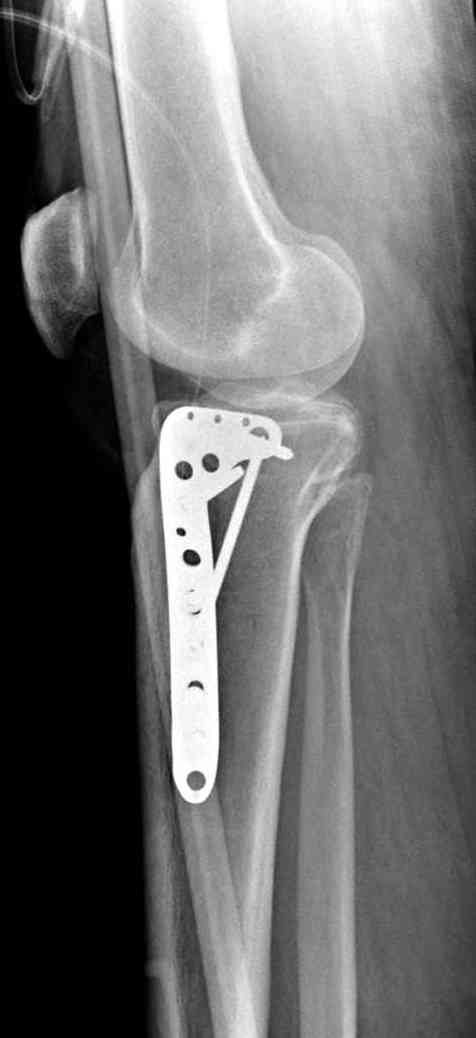

центральная импрессия, а при ипрессии с краевым переломом - после приподнимания импрессии опорная (Butress) пластина, как на снимке.